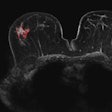

Quantitative 3D image analysis enables DCIS staging

January 1, 2014